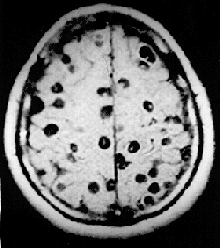

![]() Магнитно-резонансное изображение у человека с нейроцистицеркоз показывая много кист в мозге. | |

Чаще всего (более 60 %) цистицерк попадает в головной мозг, реже в скелетные мышцы и глаза. Продолжительность жизни паразита в мозге от 5 до 30 лет. В большинстве случаев в головном мозге имеются сотни и тысячи паразитов, однако встречаются и единичные цистицерки. Они локализуются в мягких мозговых оболочках на основании мозга, в поверхностных отделах коры, в полости желудочков, где они могут свободно плавать. Погибая, паразит обызвествляется, однако, оставаясь в мозге, поддерживает хронический воспалительный процесс.

Диагностировать цистицеркоз головного мозга исключительно трудно из-за отсутствия патогномоничных симптомов. В постановке диагноза опираются на следующие особенности заболевания: множественность симптомов, указывающая на многоочаговое поражение мозга, преобладание явлений раздражения, наличие признаков повышения внутричерепного давления, смена тяжелого состояния больного периодами благополучия. Диагностике помогают рентгенографические данные, КТ, МРТ, а также эозинофилия крови и цереброспинальной жидкости, положительная РСК с цистицеркозным антигеном.